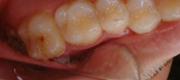

【ケース2】 虫歯治療への応用例

【治療前】

【治療後】